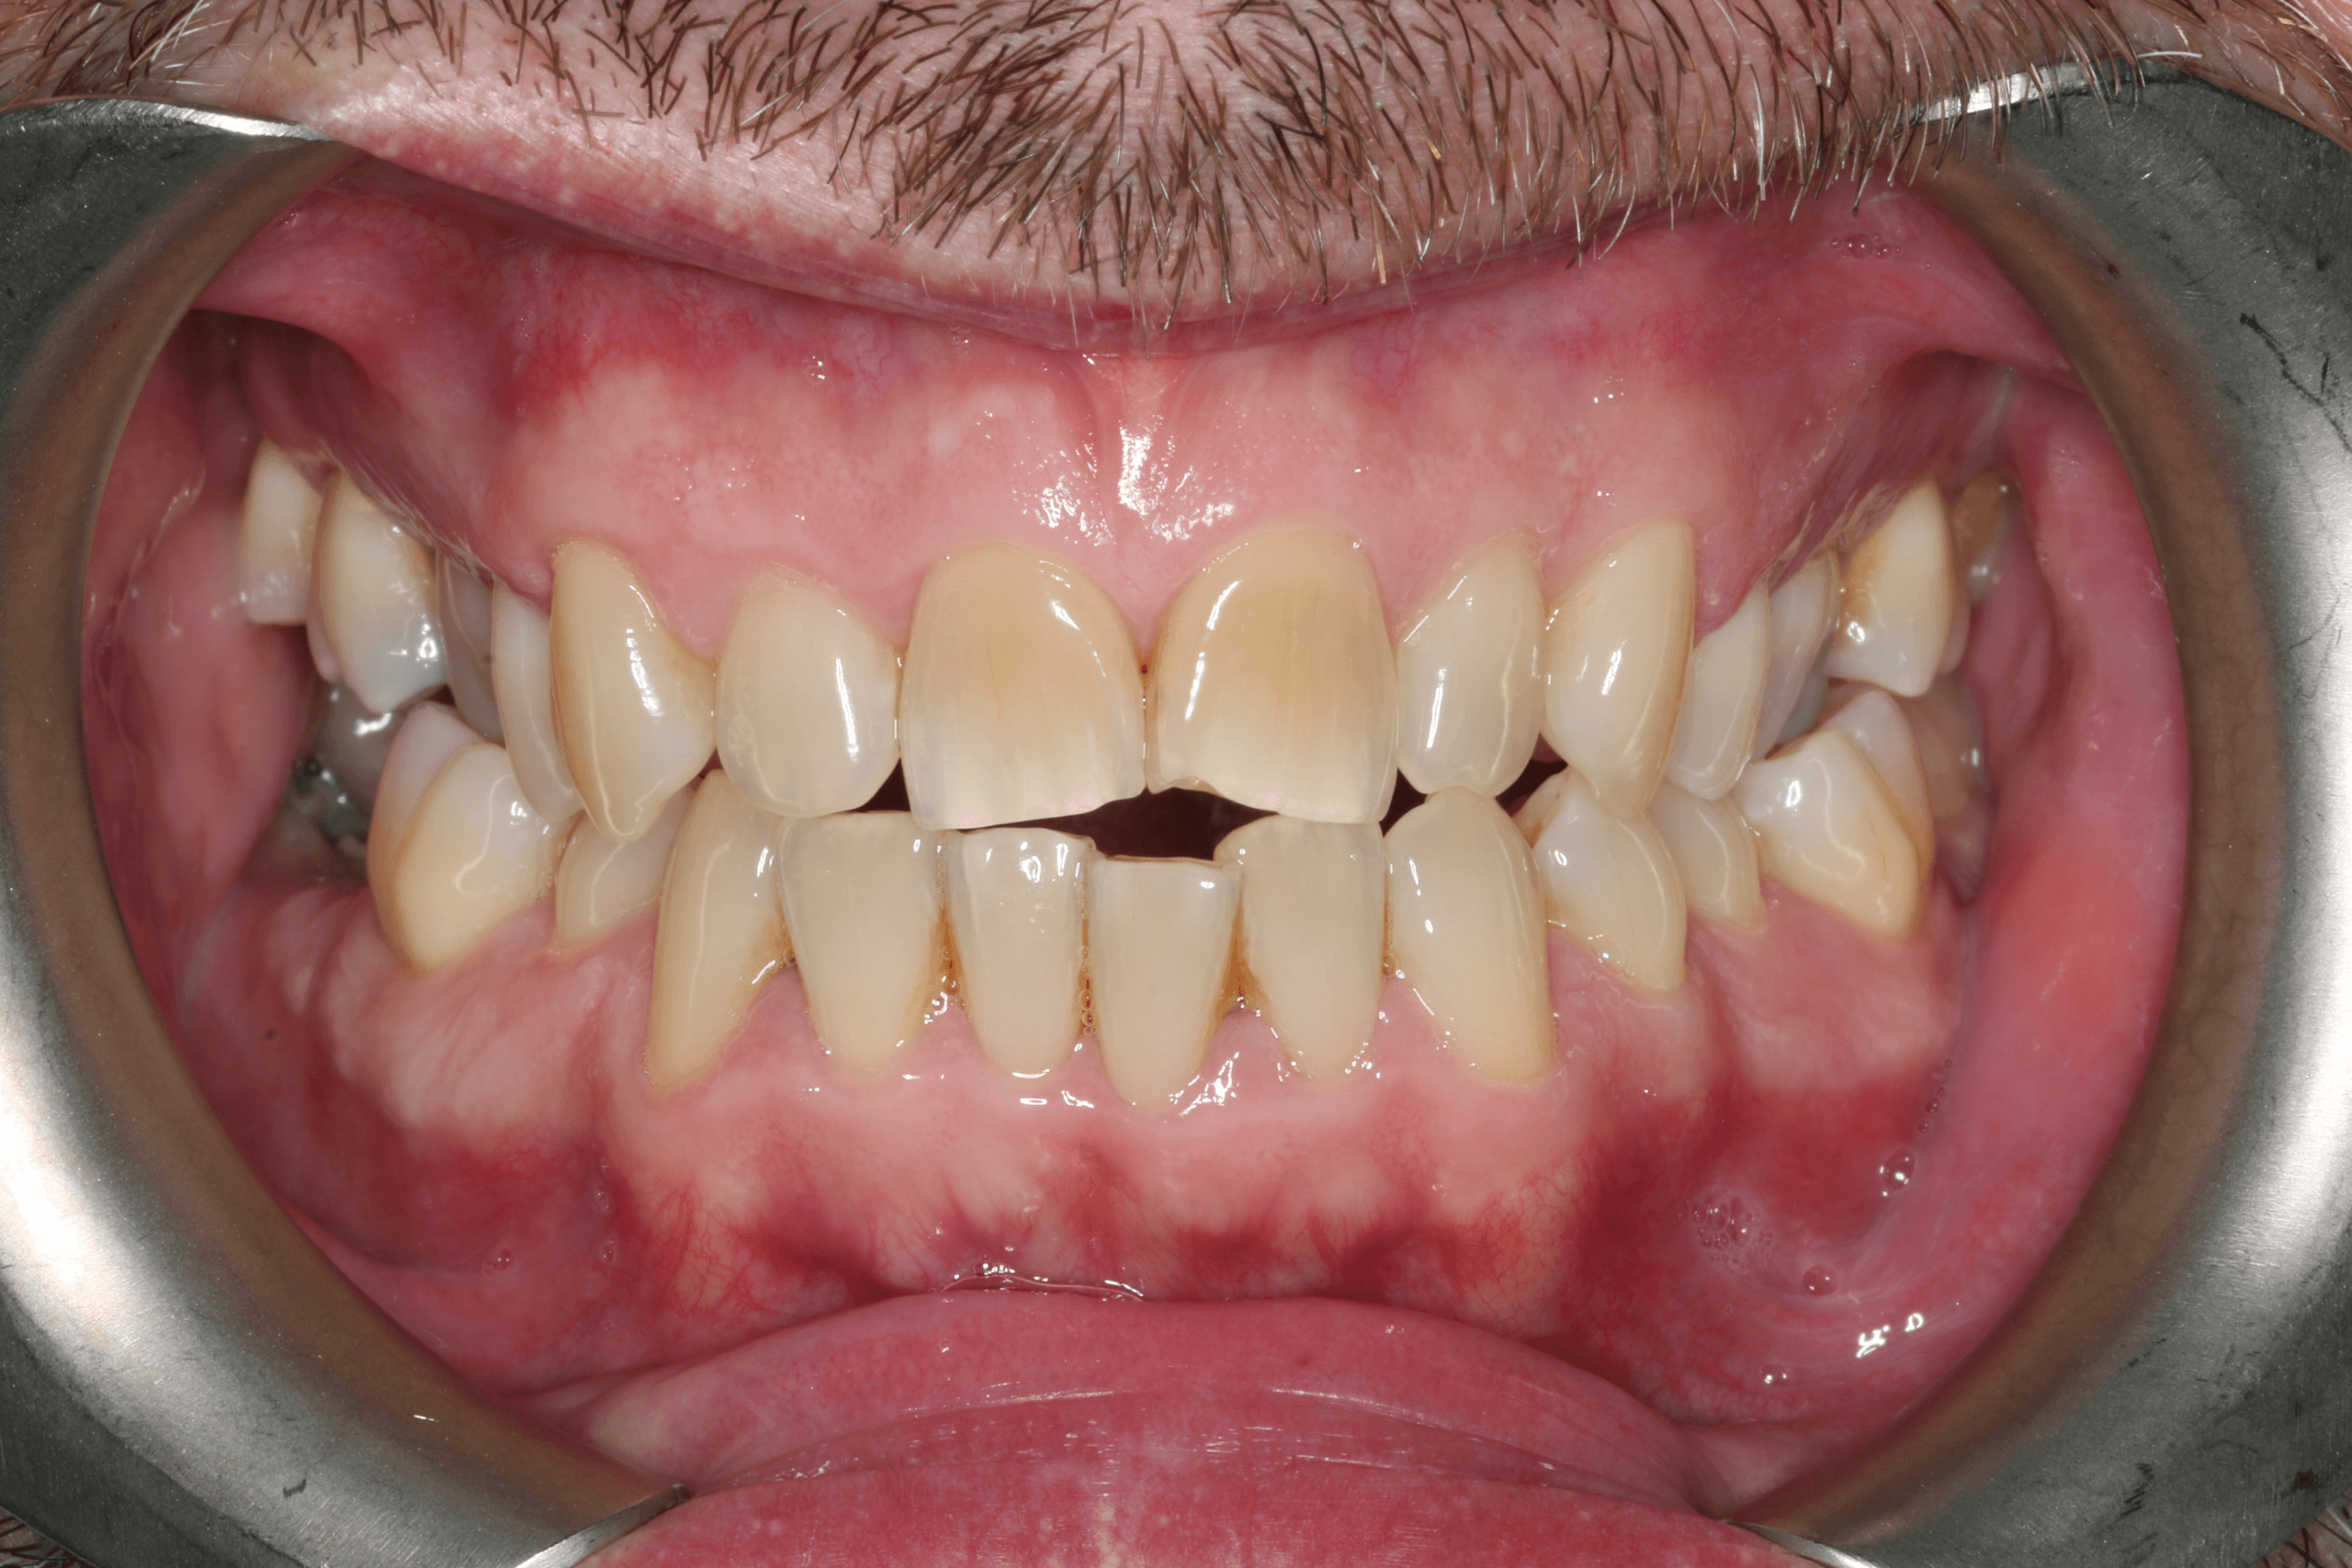

Crooked, yellow & multiple chipped teeth.

Before